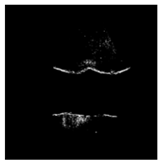

| Patient | Patient ID | Image Label | Image Prediction | Original Image | High Intensity Masking Image |

|---|---|---|---|---|---|

| Edema | 21 | Edema | Non-edema | ![]() | ![]() |

| Edema | 21 | Non-edema | Edema | ![]() | ![]() |

| Non-edema | 2 | Non-edema | Edema | ![]() | ![]() |

| Non-edema | 5 | Non-edema | Edema | ![]() | ![]() |

| Non-edema | 20 | Non-edema | Edema | ![]() | ![]() |

| Non-edema | 30 | Non-edema | Edema | ![]() | ![]() |